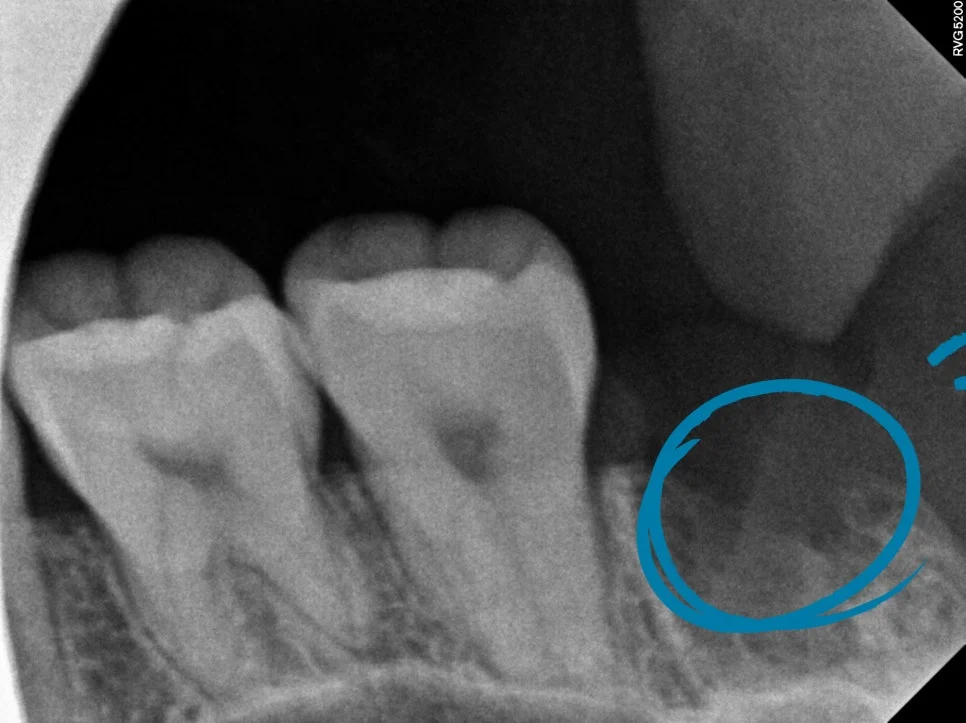

CBCT 진단 — 신경관 위치 사전 확인

CT를 보면 사랑니가 신경관과 꽤나 가까이 맞닿아 있는 상태가 확인되었습니다.

이런 경우에는 CT 검사가 선택이 아니라 필요한 과정인데요. 정확한 영상을 통해 발치 동선을 사전에 계획할 수 있어 신경 손상과 같은 위험 요소를 대폭 줄일 수 있습니다.